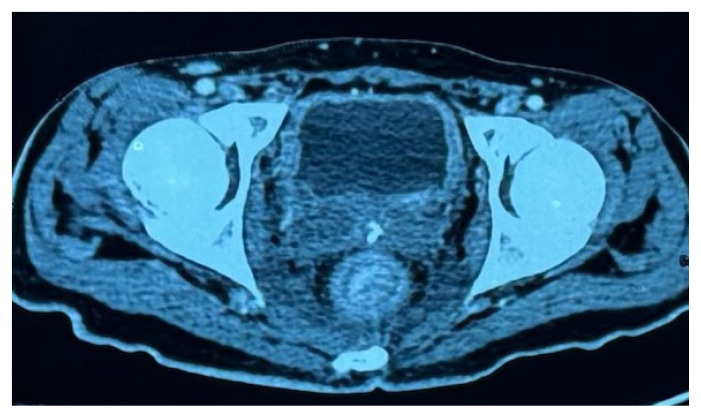

转移到直肠是非常罕见的,通常是由乳房,胃肠道和泌尿生殖系统的原发引起的。我们在这里报告一个病例急性肠梗阻引起一个不寻常的直肠狭窄,他接受了转移口。在对直肠狭窄的病因进行广泛评估后,他被诊断为弥漫性胃癌并伴有Schnitzler转移到直肠粘膜下层。这是一种不寻常的转移类型,非常罕见。文献中仅报道了11例此类病例。

Metastasis to the rectum is very rare and is usually caused by primaries from the breast, gastrointestinal tract, and genitourinary system. We report here a case of acute intestinal obstruction caused by an unusual rectal stenosis, for which he underwent a diversion stoma. On extensive evaluation for the etiology of the rectal stenosis, he was diagnosed with diffuse gastric cancer with Schnitzler's metastasis to the rectal submucosa. This is an unusual type of metastasis, very rarely seen. Only 11 such cases have been reported in the literature.